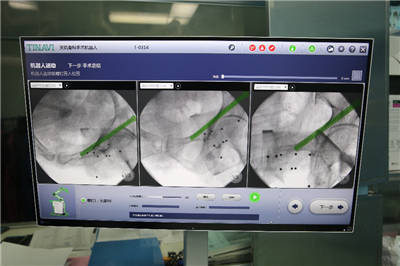

卢山副主任及吴奎副主任根据采集资料,规划手术路径:

规划路径: